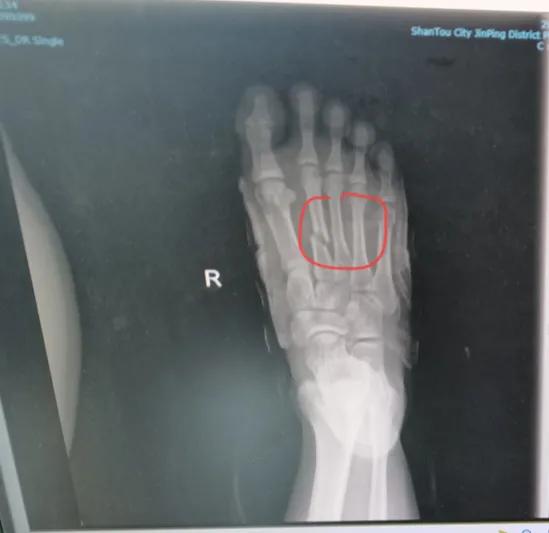

17岁男生,在学校喜欢打篮球,前几天在打球的时候,被同学不小心踩了一脚,一下子就肿了起来,巨疼,不能走路了。#儿童骨科医生邱俏峰#

学校老师赶紧把他送去医院,检查发现3根跖骨骨折,老师通知了家长,同学都家长也赶到,还带了位“骨科”诊所医生,据说是他们的朋友,而且骨科技术很厉害。

跖骨骨折的该怎么治疗?

1. 无移位或轻度移位的跖骨骨折,可以使用保守治疗,如石膏固定,固定时间一般为4~6周。

2. 对于有移位的跖骨骨折,在充分麻醉或镇痛条件下,手法复位,恢复跖骨的正常解剖位置。

3. 如果是开放性的跖骨骨折,或者移位严重,脱位的,需要彻底的清创,同时进行钢板或螺钉等内固定手术治疗。

5. 医生会根据X光片的结果来确定骨折愈合的标准。一般来说,跖骨骨折需要至少3个月的时间才能完全康复,跖骨因为承担着全身重量,如果没有愈合,不能下地负重走路。

总之,跖骨骨折的治疗需要根据骨折的移位程度、年龄、身体状况、治疗时机、以及是否有基础疾病等因素,医生会综合制定治疗方案。